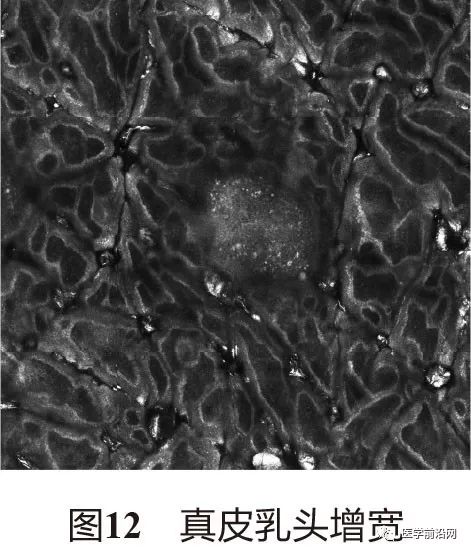

3.2 光泽苔藓 表皮萎缩变薄,真皮乳头增宽(图12),基底细胞环模糊(图13),中央可见不等量高折光的噬黑素细胞及其他较为致密的中低折光混合炎性细胞浸润(图14)。